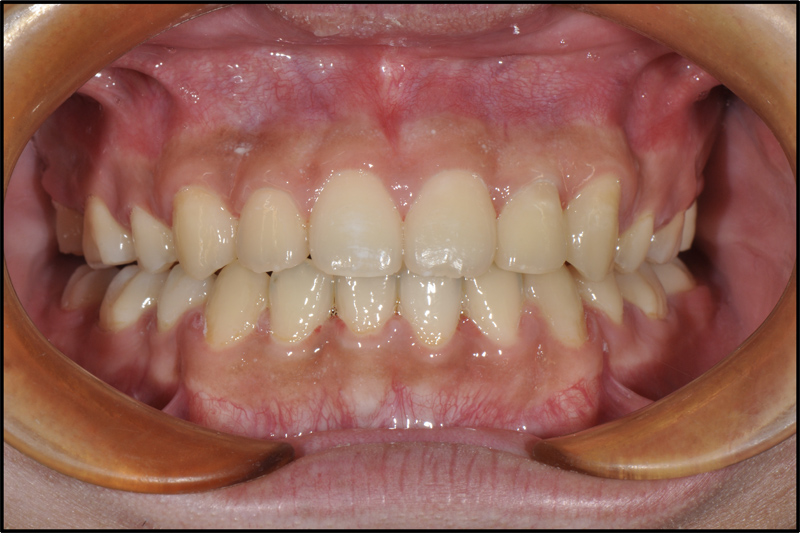

CASE 1 18歳 男

| 悩み | 上の前歯が出ていて、下の前歯がガタガタしている。 |

|---|---|

| 抜歯 | 上下小臼歯4本 |

| 装置 | マルチブラケット(表)、アンカースクリュー (2本) |

| 内容 | 前歯が前方に傾いていて口元が突出してたため抜歯を選択し、アンカースクリューを使って前歯を後ろに下げる治療を行った。しっかり前歯でかめるようになり、口元の突出感もなくなった。 |

| 期間 | 2年3ヶ月 |

| リスク | う蝕、歯周病、歯根吸収、アンカースクリュー 脱落 |

| 費用 | 70万円(調整料は含みません) |